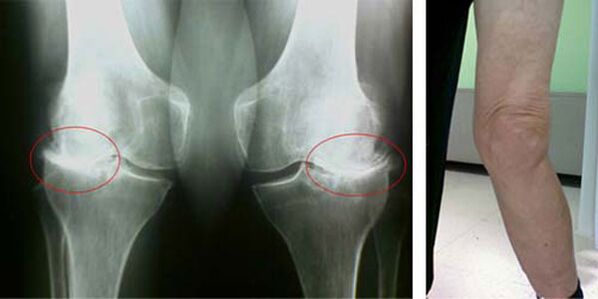

The initial stages of the occurrence of such a pathology, such as arthrosis of the knee joint, do not manifest visually in any way. However, after a period of time, the patient notices signs of knee deformity as well as characteristic curvature along the axis of the lower leg (directed inward). There is also a crack when you need to bend your legs.

The presence of pain, limited movement of the knee causes a person to see a doctor and undergo an examination. To do this, you must pass the tests and take an x-ray of the patient's joint. If these measures are not sufficient to confirm knee arthrosis, magnetic resonance imaging is performed. Based on the data collected, the doctor will select the best treatment methods.